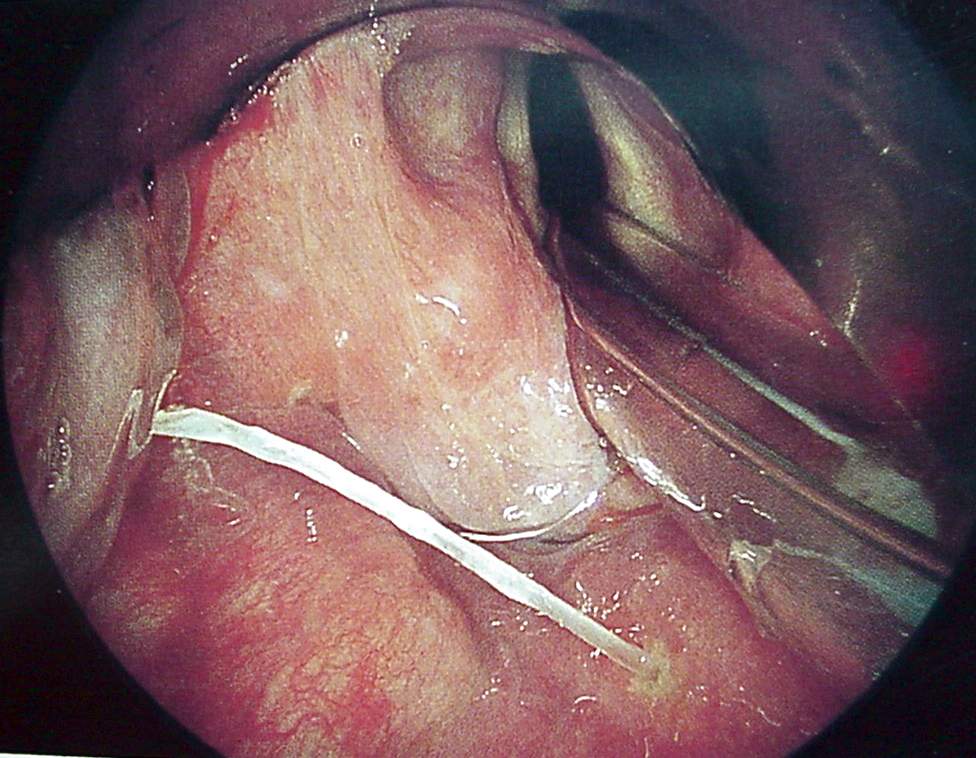

Pharynx and Esophagus Clinical Photos for Static Stations